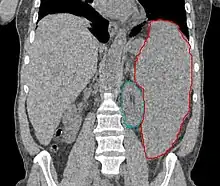

- Splenomegaly or rarely hepatomegaly